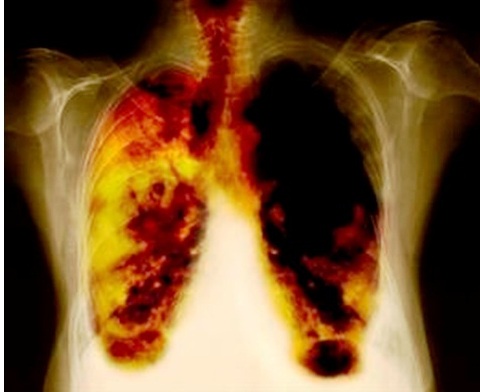

Mesotelioma maligno (flechas amarillas) con efusión pleural (asterisco amarillo). Leyenda:

1. Pulmón derecho,

2. columna vertebral,

3. Pulmón izquierdo,

4. Costillas,

5. Aorta,

6. Bazo,

7. Riñón izquierdo,

8. Riñón derecho,

9. Hígado.

Los primeros informes que relacionaban el cancer de pulmón y el asbesto datan de 1935.[6] El cáncer producido por el asbesto no aparece inmediatamente, sino que se manifiesta después de varios años (el mesotelioma pleural suele tener un tiempo de latencia de entre 20 y 40 años). Los estudios en trabajadores sugieren también que respirar asbesto podrían aumentar las posibilidades de contraer cáncer en otras partes del cuerpo (estómago, laringe, intestino, esófago, páncreas y los riñones). La identificación y el tratamiento tempranos de todo cáncer pueden aumentar la calidad de vida y la supervivencia de la persona.